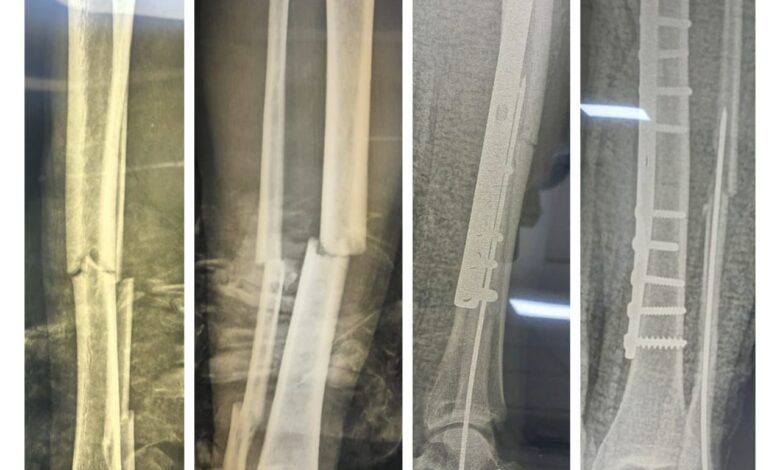

استقبلت طوارئ مستشفى حوطة بني تميم العام مقيمًا يبلغ من العمر 49 عامًا، تعرض لحادث مروري أسفر عن كسر مغلق في عظمتي الساق.

وتمكن الفريق الطبي في قسم العظام من التعامل مع الحالة بكفاءة واحترافية، حيث أُجريت جراحة دقيقة باستخدام تقنية التثبيت البيولوجي دون الحاجة إلى فتح الجلد والأنسجة المحيطة بالكسر. وقد تم التثبيت من خلال فتحات صغيرة لوضع الشريحة وتثبيتها باستخدام المسامير.

يذكر أن هذه التقنية التي يمكن استخدامها في بعض الحالات تُعد من الأساليب المتقدمة التي تساهم في تسريع التئام الأنسجة ولحام الكسور، بفضل حفاظها على التغذية الدموية للكسر، مما يُسهم في تعزيز جودة الرعاية الصحية المقدمة.